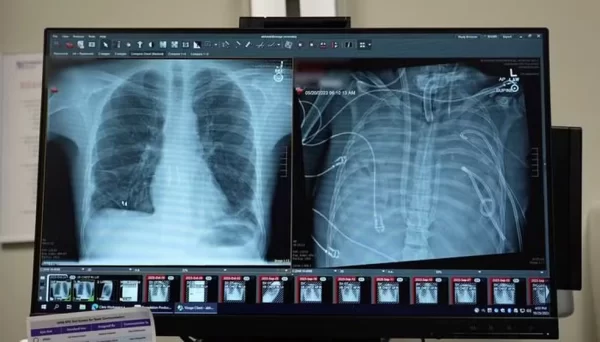

Os médicos retiraram os dois pulmões e instalaram o dispositivo, que oxigenava o sangue, removia o dióxido de carbono e mantinha o fluxo sanguíneo necessário para o coração e o restante do corpo, permitindo que o paciente permanecesse vivo enquanto se recuperava da infecção sistêmica.

O resultado surpreendeu a equipe médica. Assim que os pulmões foram removidos, o homem começou a apresentar melhora. A pressão arterial se estabilizou, outros órgãos passaram a funcionar melhor e a infecção cedeu.

Em dois dias, o quadro clínico mudou completamente, e ele pôde receber o transplante. Hoje, cerca de dois anos após o procedimento, leva uma vida normal.